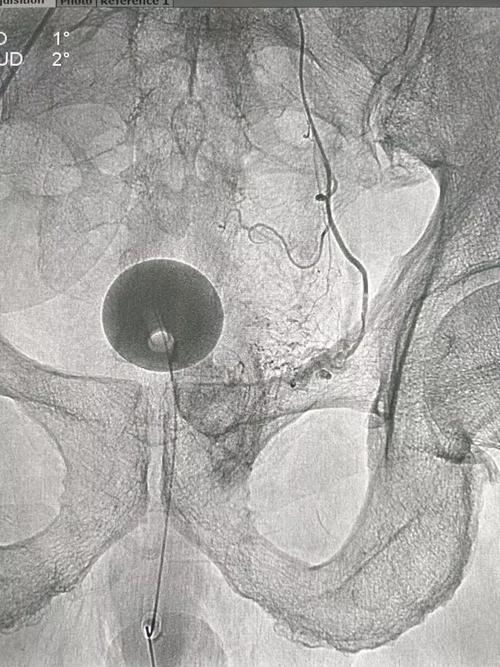

避开左侧膀胱动脉,继续向前将微导管超选至左侧前列腺动脉,经微导管

左侧前列腺动脉栓塞术后,造影复查示:左侧前列腺动脉主干闭塞.

介入微创治疗前列腺增生新方法—超选择插管前列腺动脉造影术 动脉

术前血管造影可见右侧前列腺血管丰富,前列腺染色明显